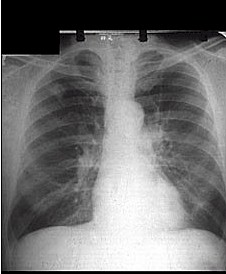

原發性支氣管肺癌的診斷依據包括:症狀體徵x線表現以及痰癌細胞檢查(痰檢)診斷工作中應根據不同情況採取不同步驟

肺癌1.凡無症狀但具有三大高危因素(男性年齡≥45歲和吸菸>400支/年)者應半年進行70~100mm螢光縮影x線攝片或胸部透視和痰液細胞檢查

(三)X線陽性痰檢陰性

(四)X線陽性痰檢陽性